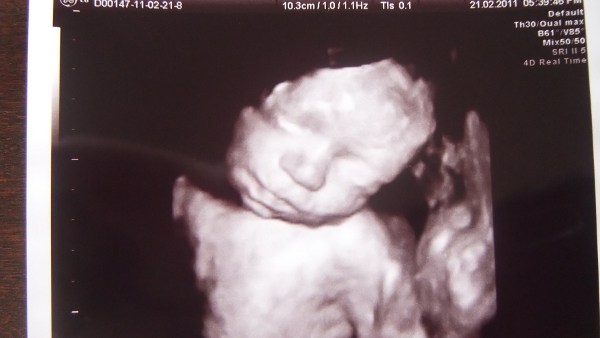

No, nem kéretem magam tovább, íme a babák :)

Kép Miksa 26+3

Kép Stefánia 19+3

Stefi már nem mutogatja magát (ez a19 hetes fotó is hosszas unszolásra készült a genetikai uh-n)

Oroszagár, csodálatosanszépségesengyönyörűek a bébikék :lol: Olyan hihetetlenek ezek a felvételek...

De gyönyörűek! Hihetetlen, hogy már ismerheted őket, a mozdulataikat, mielőtt a kezedbe vennéd őket! Csodálatos, nem?

Köszi lányok, tényleg csoda ez az ultrahang. Mennyi minden törént mióta megszülettünk! Akkor még nem volt uh (legalábbis itt nem csináltak), az első lombikbaba is utánam született :D Nagyon jó nézegetni őket, és most már hason keresztül is lehet velük játszani, nagyon vicces, ahogy átrendezik a hasam formáját néha :D De ezt ti is mind meg fogjátok tapasztalni :!: